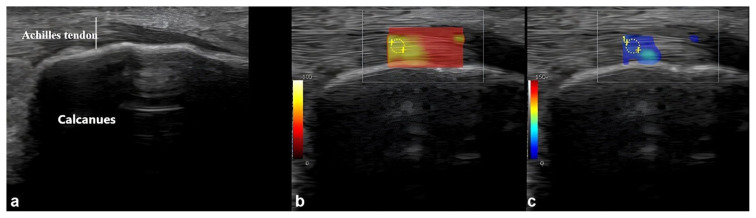

背景/目的:本研究的主要目的是比较健康志愿者和2型糖尿病(T2DM)患者足底筋膜(PF)和跟腱(AT)的厚度和刚度。次要目的是探讨无周围神经病变或足部溃疡、有周围神经病变或足部溃疡的T2DM患者中PF和AT的厚度和硬度与糖尿病病程(以月为单位)和血红蛋白A1c (HbA1c)水平之间的相关性。材料和方法:共纳入289名参与者,包括117名健康志愿者(A组)和172名T2DM患者(59.5%),年龄、性别和体重指数相匹配。T2DM队列分为三个亚组:B组(无周围神经病变或足部溃疡),C组(有周围神经病变)和D组(有足部溃疡)。采用超声(USG)和剪切波弹性成像(SWE)评估PF和AT特性,并分析其与糖尿病病程和HbA1c水平的相关性。结果:与健康对照组相比,T2DM患者表现出更大的PF和AT厚度,更低的僵硬度(p < 0.001)。各亚组中,D组PF和AT厚度最大,刚度最低,C组次之,B组次之(p < 0.001)。糖尿病病程、HbA1c水平和肌腱厚度呈正相关,而与肌腱僵硬呈负相关(均p < 0.001)。结论:USG和SWE显示,与健康个体相比,T2DM患者的PF和AT特性发生了显著变化,这些变化与糖尿病的严重程度和持续时间有关。

Material and methods: A total of 289 participants, including 117 healthy volunteers (Group A) and 172 T2DM patients (59.5%), matched for age, sex, and body mass index, were included. The T2DM cohort was stratified into three subgroups: Group B (without peripheral neuropathy or foot ulcers), Group C (with peripheral neuropathy), and Group D (with foot ulcers). Ultrasonography (USG) and shear wave elastography (SWE) were used to assess PF and AT properties, and correlations with diabetes duration and HbA1c levels were analyzed.